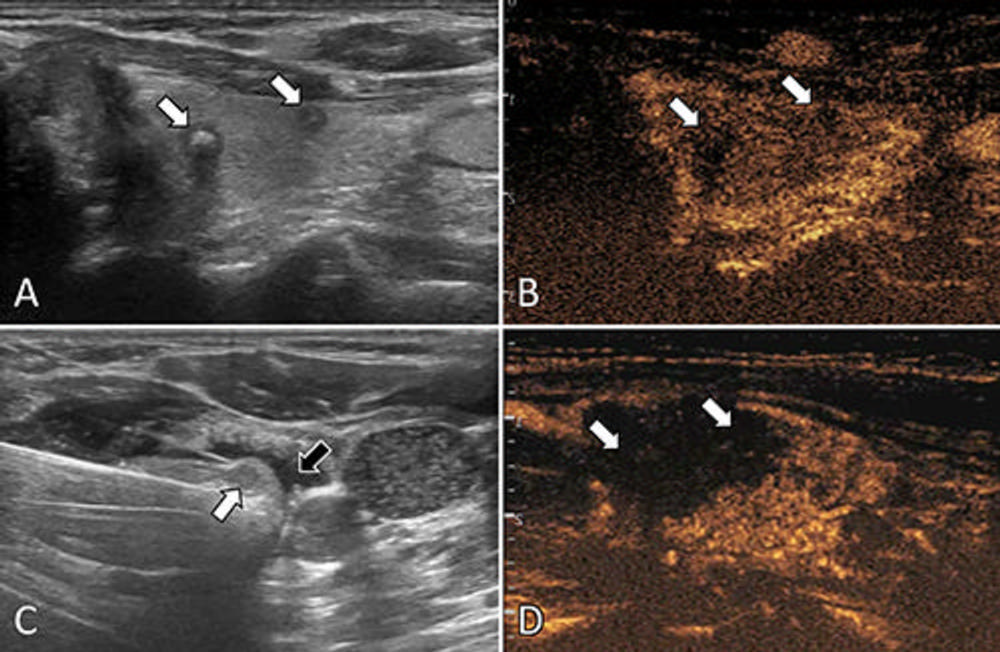

Figure 2. Ultrasound (US) images in a 57-year-old female patient with multifocal papillary thyroid carcinoma (PTC). (A) Routine US scan shows two hypoechoic PTC nodules (arrows) in the left lobe. (B) Preablation contrast-enhanced US image shows hypoenhancement in the arterial phase (arrows). (C) Isolating fluid (black arrow) is used to protect the muscles beside the nodule (white arrow) during the ablation. (D) Postablation contrastenhanced US image shows no enhancement in the original tumor zone (arrows).